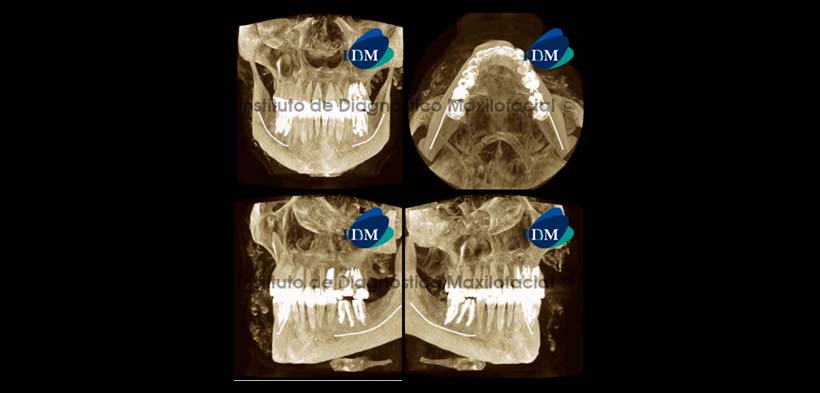

La tomografía computarizada de haz cónico en vista coronal nos muestra múltiples imágenes hiperdensas de forma irregular localizadas en la región correspondiente a los tejidos blandos de la región maxilofacial y que se encuentran con cierto predominio en el lado derecho (Fig. 1). Signos tomográficos compatibles con calcificaciones en tejidos blandos, descartar Calcinosis Cutis.

La reconstrucción 3D en la opción radiográfico matizado nos muestra preponderantemente las estructuras con alto contenido mineral como el tejido óseo. En este caso las calcificaciones en tejidos blandos son visualizadas con un aspecto puntiforme y con una distribución irregular (Fig. 6).